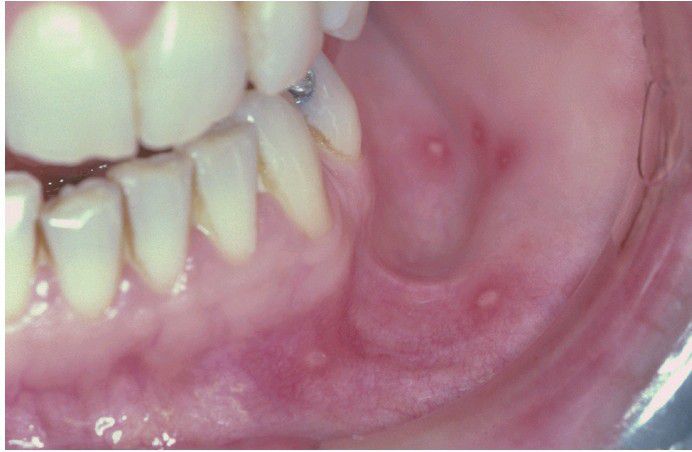

Hand-foot-and-mouth Disease.

Multiple aphthous-like ulcerations of the mucobuccal fold.